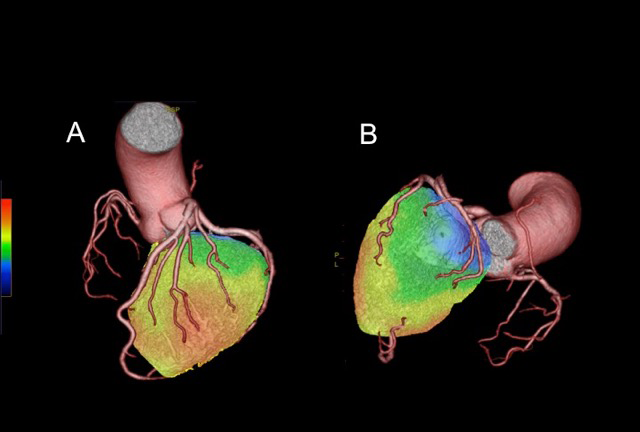

Figure 1: Fusion imaging in patients with organic stenosis in right coronary artery. Culprit lesions of ischemia were determined in both A and B.